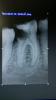

Ico Опубликовано 14 августа, 2013 Поделиться Опубликовано 14 августа, 2013 Преэндо(СИЦ),первичная инструменталка,разрез и дренаж.Второе посещение - паковка,латералка.В апексе 40.02,на работчеи 30.04 профаил. 8 Ссылка на комментарий

Чертков Александр Опубликовано 14 августа, 2013 Поделиться Опубликовано 14 августа, 2013 Преэндо(СИЦ),первичная инструменталка,разрез и дренаж.Второе посещение - паковка,латералка.В апексе 40.02,на работчеи 30.04 профаил.Очень достойно для латералки. Я про паковку. Ссылка на комментарий